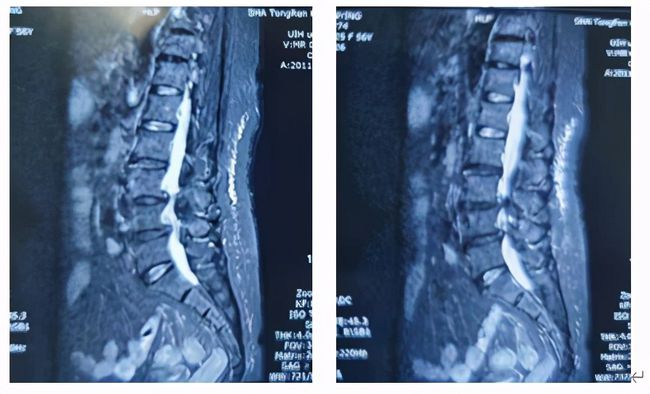

近期,邵女士前往上海交通大学医学院附属同仁医院脊柱外科就医,X线检查,腰4椎体轻度滑脱并有退变性侧弯,MR检查提示椎间盘突出,椎管明显狭窄,黄韧带肥厚、硬膜囊及神经根受压,诊断为:腰椎滑脱伴椎管狭窄症。